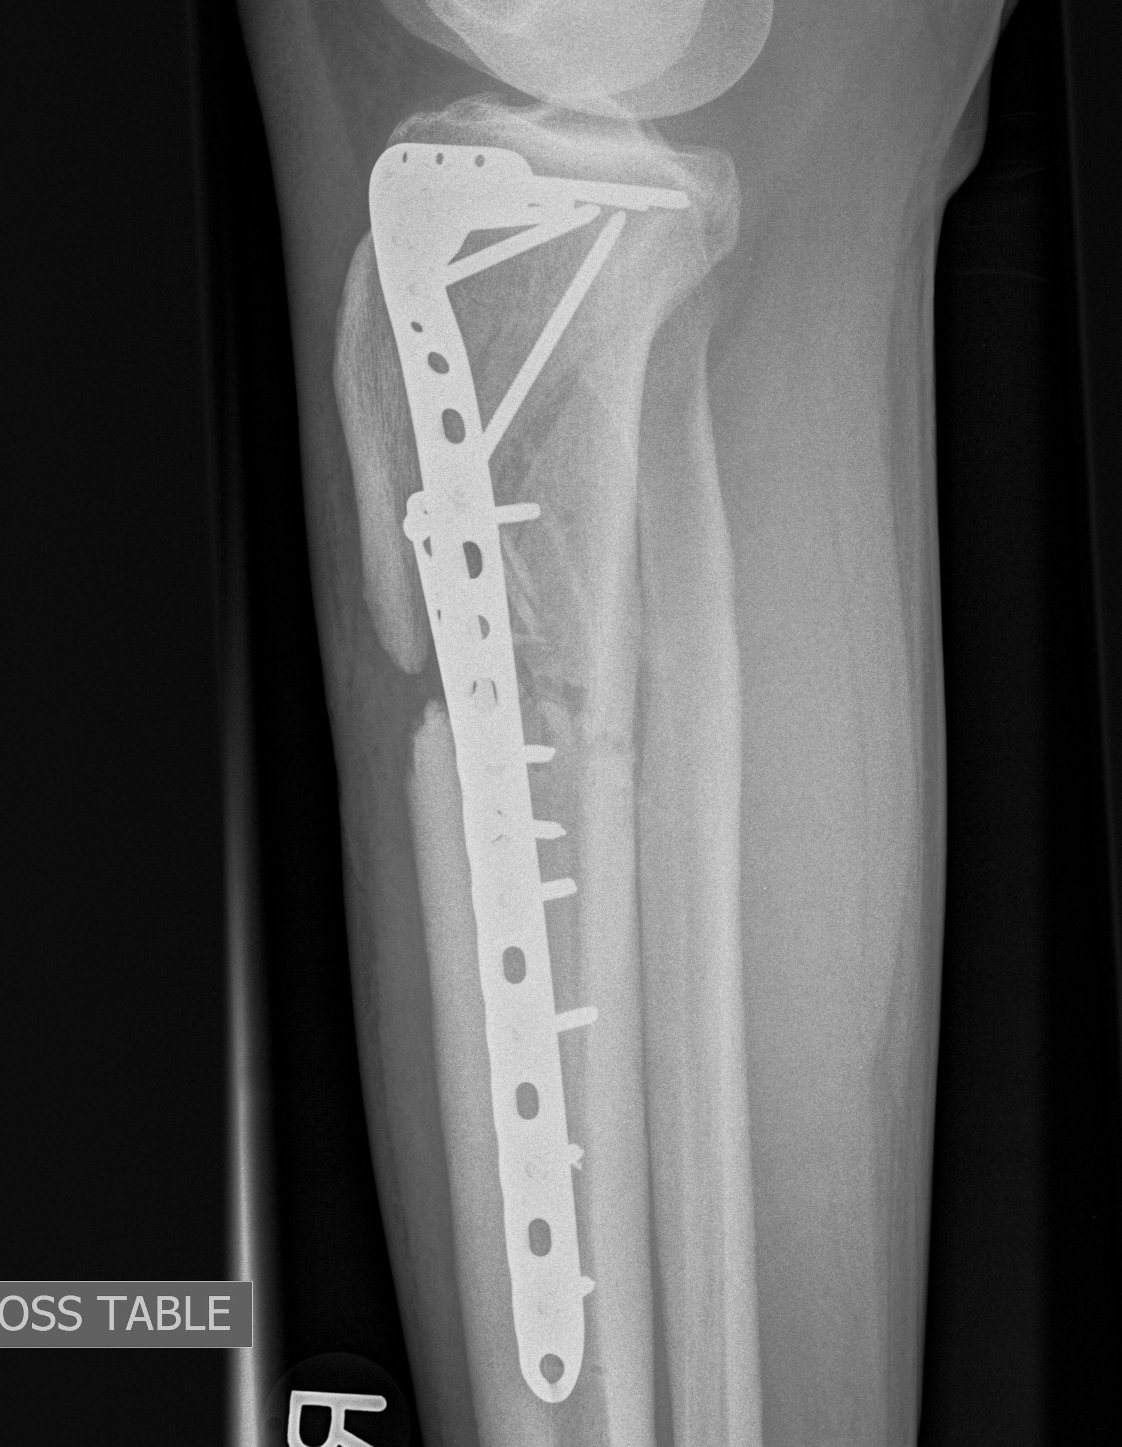

Type II Split Depression

Timing

- blisters epithelialised

- skin wrinkled

- 2-3 weeks

Technique

- elevate and restore joint line

- compress with bone reduction forcep

- stabilise joint line with 2 x 6.5 mm cannulated partially threaded screws

- check fluoroscopy

- restore alignment via application anatomically contoured 4.5 mm locking plate

- often use BG or substitutes under depression fractures laterally